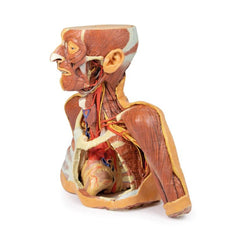

3D Printed Head, Neck, Shoulder and Thorax Replica with Angiosomes

The head and neck of the specimen provides views of both superficial and deep structures in the region. The calotte has been removed ~2cm superior to the orbits to expose the brain in relation to the endocranial cavity. The transverse section through the cerebrum demonstrates the relation of the grey matter cortex to the white matter medulla, as well as the lateral ventricles with a small amount of choroid plexus visible in the base of both spaces. The skin and superficial fascia on the right side has been retained and false-coloured to display the angiosomes of the face and posterior neck. On the left side, the superficial tissues have been dissected to expose the muscles of facial expression, muscles of mastication, and deeper structures of the infratemporal fossa including the lingual nerve, terminal branches of the external carotid artery into the superficial temporal and maxillary arteries.

The carotid sheath has been opened on both sides of the neck, and the internal jugular veins and sternocleidomastoid muscles largely removed, to expose the pathway of the common carotid arteries, internal and external carotid arteries, and the vagus nerves. On the right side, the great auricular nerve ascends towards the face, while the hypoglossal nerve can be seen adjacent to the exposed stylohyoid ligament and supra- and infrahyoid muscles. A large thyroid gland is present bilaterally inferior to the thyroid cartilage, with a well-preserved superior thyroid artery and inferior thyroid vein on the right side and across the midline.

The root of the neck – axillary junction:

The clavicle has been partially removed on the left side of the specimen (medial to the origin of the deltoid) to expose the first rib and the insertion of anterior scalene muscle. The roots of the brachial plexus (C5-T1) can be seen forming the trunks posterior to this muscle but anterior to middle and posterior scalene muscles they emerge from the interscalene plane. While the subclavian vein has been removed, the subclavian artery is also seen passing behind the scalenus anterior. The transition of the subclavian artery to the axillary artery is exposed, as is its position relative to the cords of the brachial plexus (medial, lateral and posterior).

The left axilla has been dissected to expose the divisions and cords of the brachial plexus and its major and minor branches. The contributions from the medial and lateral cords coming together around the axillary artery to form the median nerve is very distinctive. The course of the medial cord, the ulnar nerve, is clearly visible as is the musculocutaneous nerve as the continuation of the lateral cord. The axillary nerve is seen wrapping posteriorly around the surgical neck of the humerus. The thoracodorsal nerve and artery are seen descending on the medial wall of the axilla to enter the latissimus dorsi muscle. The long thoracic nerve is seen just anterior to this upon the serratus anterior muscle which it supplies.

The axilla/root of neck junction on the right is similar except the clavicle (and subclavius muscle) has been retained, which gives an appreciation of the dimensions of the cervico-axillary canal through which structures gain entry to the axilla. Also on the right side the pectoralis minor and major (that comprise the anterior axillary wall) have been reflected with only a small portion of their insertions being retained.

Thorax:

The thorax has been opened via a ‘window’ on the left to display the internal thoracic wall and mediastinum. The left lung has been removed and the intercostal spaces are discernable deep to the parietal pleura although intercostal neurovascular bundles are only discernable posteriorly. The pericardium has been removed to expose the heart with its apex pointing inferiorly, anteriorly, and to the left. The left side of the heart is exposed as are the left pulmonary veins and arteries (above left main bronchus), ascending aorta, aortic arch and commencement of the descending thoracic aorta. The left vagus nerve and left recurrent laryngeal nerve are easily identified. The right half of the anterior and lateral thoracic wall are intact and display the muscles of the intercostal spaces and inserting hypaxial muscles from the right upper limb. If the specimen is viewed from below, the right lung and pleural spaces along with the diaphragmatic surface of the heart are all evident. While the skin and superficial fascia posterior thorax has been left intact, the distribution of cutaneous branches of dorsal rami have been illustrated along the left side of the specimen.

This large, multipart 3D printed specimen displays a great deal of anatomy spanning the head, neck, thorax and upper limbs.Head and neck:

The head and neck of the specimen provides views of both superficial and deep structures in the region. The calotte has been removed ~2cm superior to the orbits to expose the brain in relation to the endocranial cavity. The transverse section through the cerebrum demonstrates the relation of the grey matter cortex to the white matter medulla, as well as the lateral ventricles with a small amount of choroid plexus visible in the base of both spaces. The skin and superficial fascia on the right side has been retained and false-coloured to display the angiosomes of the face and posterior neck. On the left side, the superficial tissues have been dissected to expose the muscles of facial expression, muscles of mastication, and deeper structures of the infratemporal fossa including the lingual nerve, terminal branches of the external carotid artery into the superficial temporal and maxillary arteries.

The carotid sheath has been opened on both sides of the neck, and the internal jugular veins and sternocleidomastoid muscles largely removed, to expose the pathway of the common carotid arteries, internal and external carotid arteries, and the vagus nerves. On the right side, the great auricular nerve ascends towards the face, while the hypoglossal nerve can be seen adjacent to the exposed stylohyoid ligament and supra- and infrahyoid muscles. A large thyroid gland is present bilaterally inferior to the thyroid cartilage, with a well-preserved superior thyroid artery and inferior thyroid vein on the right side and across the midline.

The root of the neck – axillary junction:

The clavicle has been partially removed on the left side of the specimen (medial to the origin of the deltoid) to expose the first rib and the insertion of anterior scalene muscle. The roots of the brachial plexus (C5-T1) can be seen forming the trunks posterior to this muscle but anterior to middle and posterior scalene muscles they emerge from the interscalene plane. While the subclavian vein has been removed, the subclavian artery is also seen passing behind the scalenus anterior. The transition of the subclavian artery to the axillary artery is exposed, as is its position relative to the cords of the brachial plexus (medial, lateral and posterior).

The left axilla has been dissected to expose the divisions and cords of the brachial plexus and its major and minor branches. The contributions from the medial and lateral cords coming together around the axillary artery to form the median nerve is very distinctive. The course of the medial cord, the ulnar nerve, is clearly visible as is the musculocutaneous nerve as the continuation of the lateral cord. The axillary nerve is seen wrapping posteriorly around the surgical neck of the humerus. The thoracodorsal nerve and artery are seen descending on the medial wall of the axilla to enter the latissimus dorsi muscle. The long thoracic nerve is seen just anterior to this upon the serratus anterior muscle which it supplies.

The axilla/root of neck junction on the right is similar except the clavicle (and subclavius muscle) has been retained, which gives an appreciation of the dimensions of the cervico-axillary canal through which structures gain entry to the axilla. Also on the right side the pectoralis minor and major (that comprise the anterior axillary wall) have been reflected with only a small portion of their insertions being retained.

Thorax:

The thorax has been opened via a ‘window’ on the left to display the internal thoracic wall and mediastinum. The left lung has been removed and the intercostal spaces are discernable deep to the parietal pleura although intercostal neurovascular bundles are only discernable posteriorly. The pericardium has been removed to expose the heart with its apex pointing inferiorly, anteriorly, and to the left. The left side of the heart is exposed as are the left pulmonary veins and arteries (above left main bronchus), ascending aorta, aortic arch and commencement of the descending thoracic aorta. The left vagus nerve and left recurrent laryngeal nerve are easily identified. The right half of the anterior and lateral thoracic wall are intact and display the muscles of the intercostal spaces and inserting hypaxial muscles from the right upper limb. If the specimen is viewed from below, the right lung and pleural spaces along with the diaphragmatic surface of the heart are all evident. While the skin and superficial fascia posterior thorax has been left intact, the distribution of cutaneous branches of dorsal rami have been illustrated along the left side of the specimen.